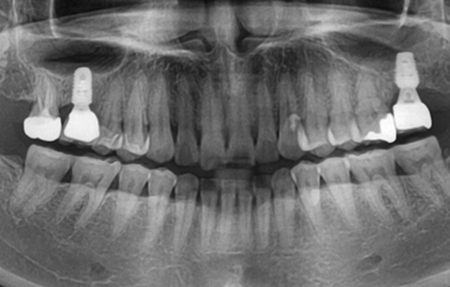

뼈이식 임플란트 치료증례

40대 여성 뼈이식 임플란트

그 이유는 뼈가 자라기 전에 그 자리를 잇몸의 살이 먼저 차지하기 때문입니다. 뼈이식을 할 때에는 이런 현상을 방지하고자 인공뼈 위에 콜라겐 차폐막을 넣어서 독립적인 공간 안에서 뼈가 영글도록 하기 때문에 발치만 하는 것보다 신생골이 형성에 유리합니다. 발치 후 뼈가 거의 다 만들어 지기를 기다리는 기간은 보통 5~6개월입니다. 이후 임플란트를 하고 다시 2~3개월 정도 기다린 뒤 치아머리 부분인 보철을 올려 마무리하게 됩니다. 발치와 동시에 임플란트 수술과 뼈 이식을 하는 경우 임플란트 보철 완성까지 3~4개월 정보 밖에 소요되지 않습니다. 따라서 발치와 동시에 식립하는 것보다 기다렸다가 임플란트 수술을 하는 것이 기간이 더 오래 걸리는 것은 사실입니다. 발치 후 기다렸다가 식립을 하는 경우는 어쩔 수 없는 경우로 뼈의 양이 부족해서 즉시 식립을 못하는 경우 필요로 하게 됩니다. 상당히 많은 환자분들께서 "발치 후 얼마나 있어도 되나요?"라고 문의하십니다. 특별한 케이스가 아니면 보통 6개월 이상이라면 대부분 자연적으로 생길 수 있는 뼈는 다 생겼다고 보고 치과에서 정밀한 검사를 통해 골 밀도와 골의 크기를 측정하여 임플란트가 가능한지 검사해 보시는 것이 좋습니다.